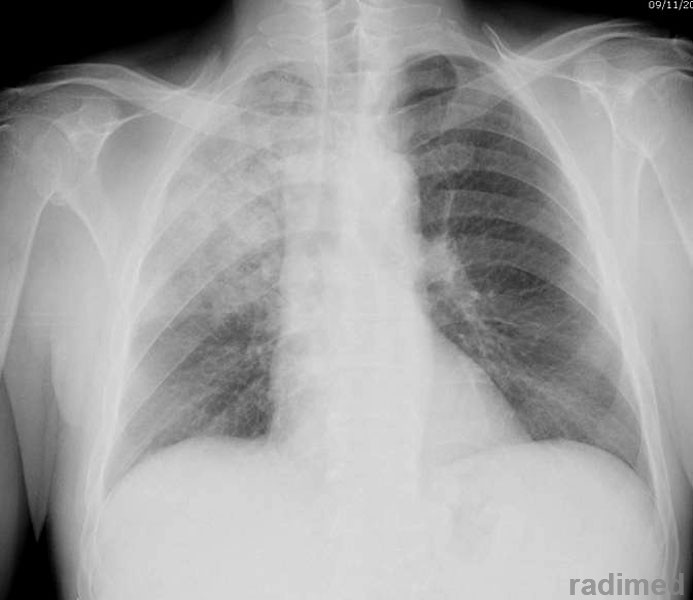

Nuevas guías para neumonía intrahospitalaria proponen acortar la duración del tratamiento